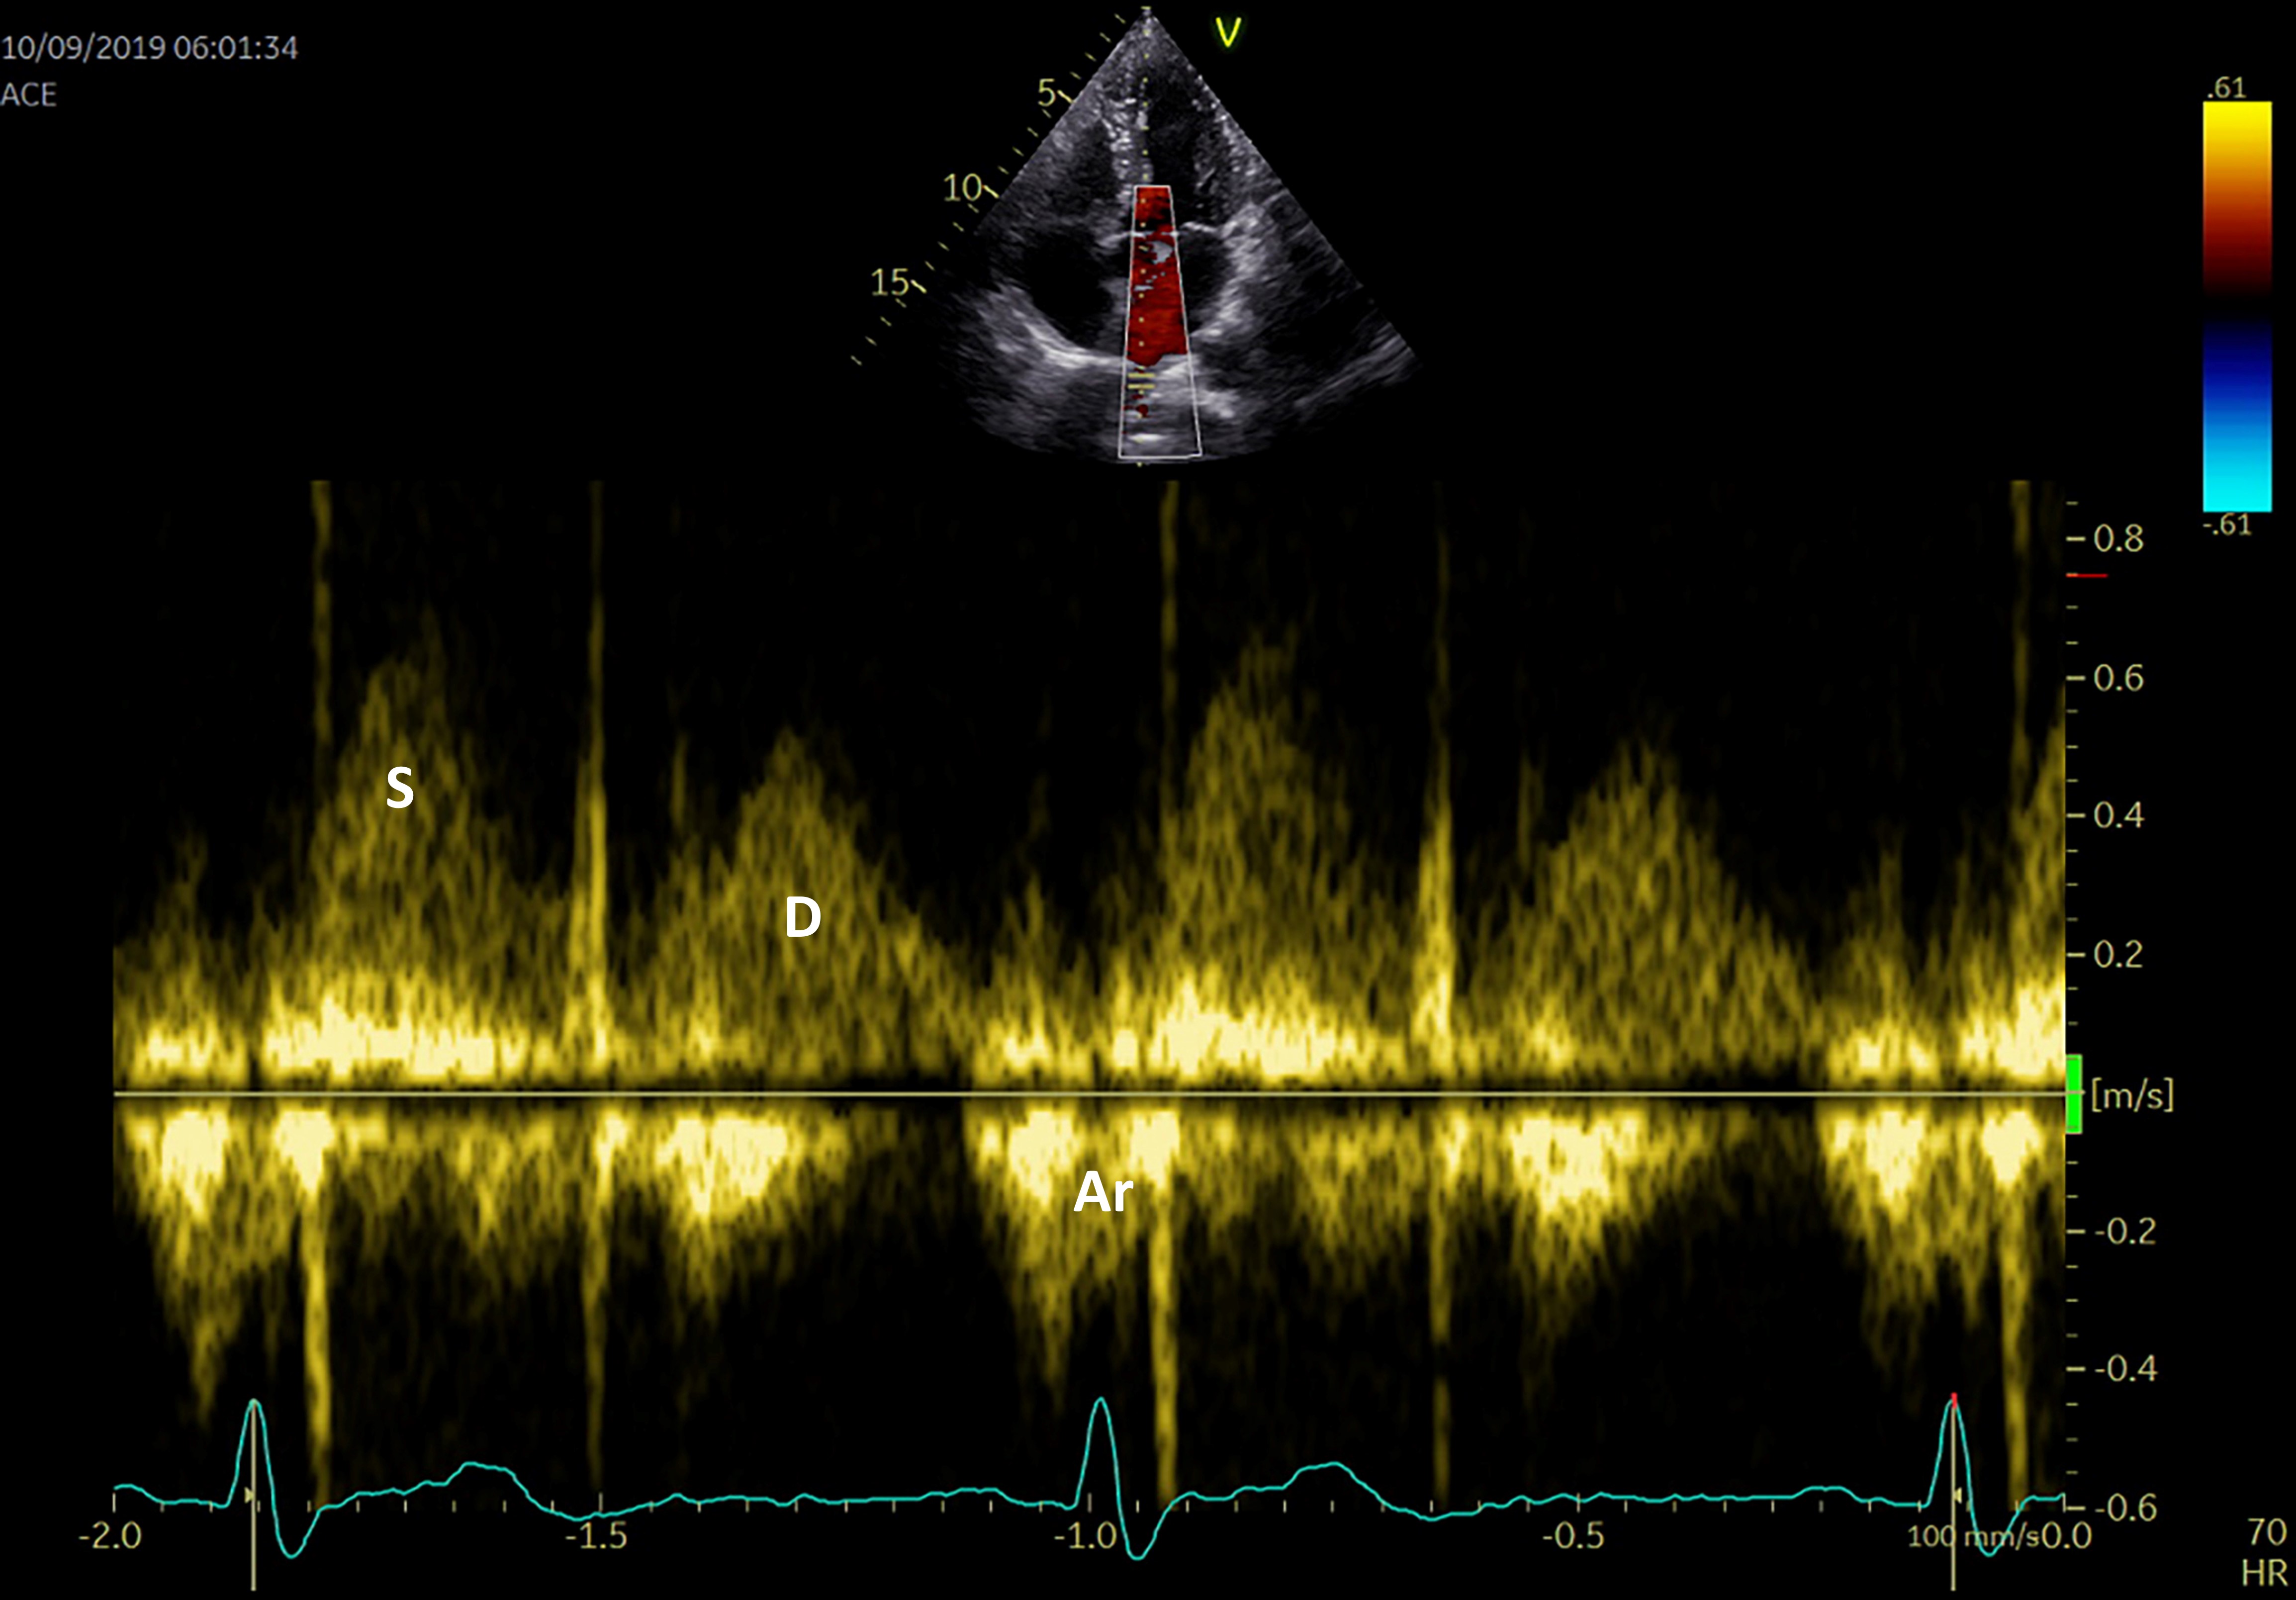

The pulmonary venous flow can also be evaluated using the sample pulse volume into one of the pulmonary veins in the apical 4-chamber view (Fig. 5). The peak systolic velocity consists in 2 waves: S1—the LA active relaxation and S2—the LA filling or reservoir function, while the peak anterograde diastolic velocity ‘D wave’ relates to the LA conduit function, and the peak retrograde diastolic velocity ‘Ar wave’ to the LA booster pump function. Although many physiological variables may affect the pulmonary venous flow aspect and velocities (age, preload, heart rate, left ventricular function), there is a significant correlation between LA pressure and S2 peak velocity, while the S2/D ratio can evaluate the LA reservoir function [66].

Fig. 5.

Fig. 5.Pulmonary venous flow using PW Doppler echocardiography S systolic flow, D diastolic flow, Ar atrial reversal.

A reduction in systolic pulmonary peak velocity is determined by increased LA pressures and is associated with increased frequency of paroxysmal AF and propensity for AF recurrence following restoration of SR. It is also correlated with a reduced LA appendage velocity flow and a higher risk of thrombus formation [67].

Pulmonary veins evaluation is not usually part of a standard echocardiographic examination, therefore prognostic information should be obtained using the mitral inflow pattern. This parameter also discloses data about the function of the left ventricle. While it can characterize LA function using hemodynamic LA capacity, the PW Doppler evaluation of the LA does not offer robust predictors of outcome.